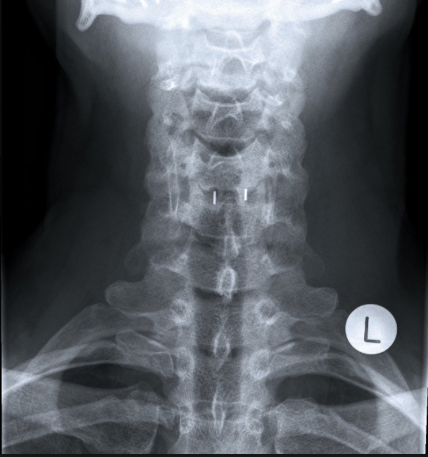

On further inspection, these sections can also be differentiated from one another morphologically (Fig. 1 1 .4). The shape of the two upper thoracic vertebrae is more similar to a cervical vertebra while the lower thoracic vertebrae gradually take on the shape of a lumbar vertebra. Only the spinous processes in the middle section of the thoracic spine slant down typically at a steep angle.

- 흉추 5-10번 시진은 구조로 감별할 수 있음.

- 상부 흉추의 형태는 경추와 유사하고, 하부 흉추의 형태는 요추와 유사함.

- 오직 중부 흉추가 기울어진 각도(아래로)로 내려가 있음.